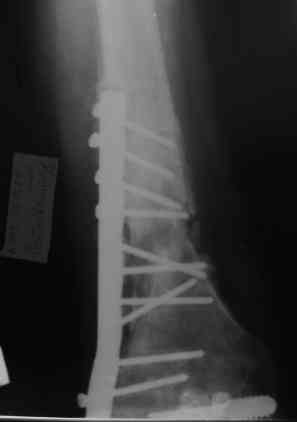

Уважаемые коллеги! Пациент лечился по поводу перелома н/3 бедра 1 год назад.

В настоящий момент: Несросшийся перелом н/3 правого бедра. Остеомиелит, свишевая форма. Контрактура коленного сустава.

Из свища скудное гнойное отделяемое. Как минимизировать количество операций, максимально улучшить качество жизни, сократить время пребывания в аппарате внешней фиксации, т.е. вернуть больного к нормальной жизни за минимальное количество ходов?

Да, стоит наверное добавить, что у нас отсутствует ЭОП. Как вы оцените следующую тактику: санация - антеградная установка спейсера на сплошном штифте + внешняя фиксация на 2 месяца - восстановление объема движений в коленном суставе?